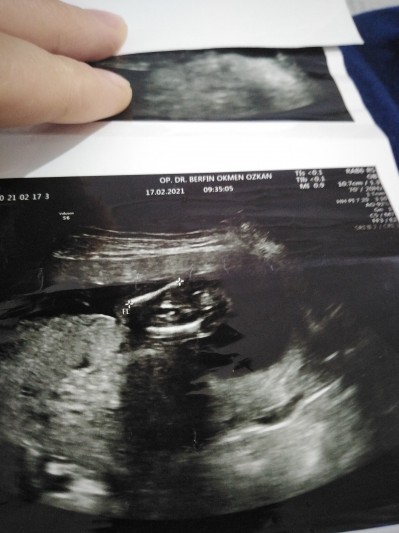

image

15 hafta

Ayakları karnına cekmiş gbi duruyor keseye göre felan tahmin bekliirom doktor kıza benziyor dedi

Yeter anne ne geldin uyandirdin beni dermiş gibi durmuş bence erkek.

Kız bebek bence canım

Kiz bence canim